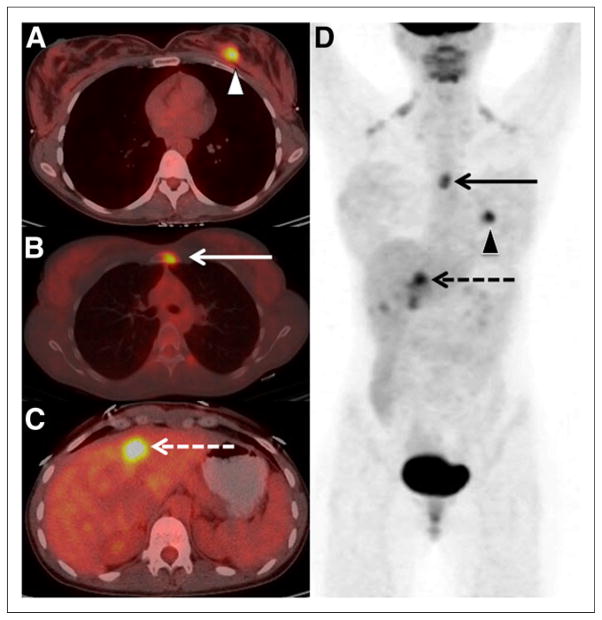

FIGURE 1.

A 29-y-old woman with clinical stage IIA breast cancer upstaged to stage IV by 18F-FDG PET/CT. Axial PET/CT images demonstrated known primary left breast cancer (arrowhead) (A), previously unknown osseous metastasis (solid arrow) (B), and previously unknown liver metastasis (dashed arrow) (C) proven by biopsy. (D) Maximum-intensity-projection PET gives overview of all lesions.